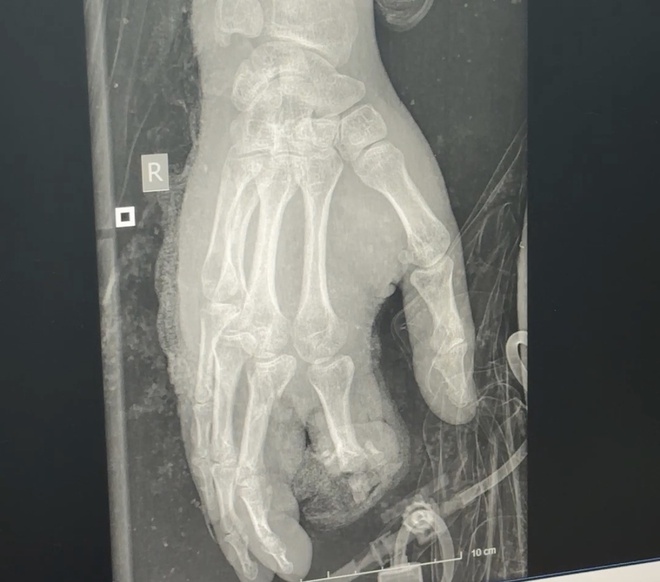

Bệnh nhân dập nát bàn tay sau tai nạn pháo nổ - Ảnh: BVCC

Đáng chú ý là trường hợp bệnh nhân 15 tuổi (trú tại Thái Nguyên) được đưa vào viện trong tình trạng dập nát cẳng bàn tay hai bên, bỏng vùng mặt, cẳng chân và thành trước ngực. Các tổn thương nghiêm trọng đe dọa trực tiếp tính mạng và khả năng lao động lâu dài của bệnh nhân.